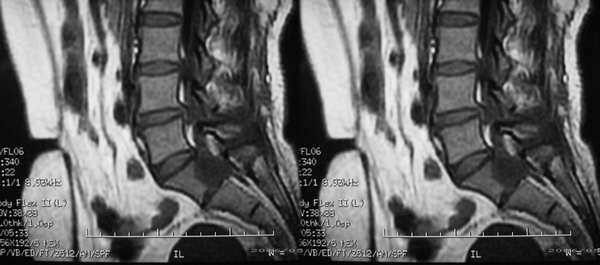

患者,女性,60岁。腰痛、腿痛一周余,临床医生考虑:椎间盘突出,行ct及mr检查

病灶为长t1长t2信号,对s1椎体是压迫吸收,应首先考虑骶管囊肿。建议增强扫描。

征象:1、骶椎管偏右侧囊性病变,长t1长t2改变,均匀。2、慢性病变过程,邻近骨质有吸收变薄。

考虑:盲囊蛛网膜囊肿。

S1椎长T1长T2信号,与蛛网膜下腔相连,边界清晰,CT可见局部骨质吸收,边缘硬化改变。支持骶管囊肿。